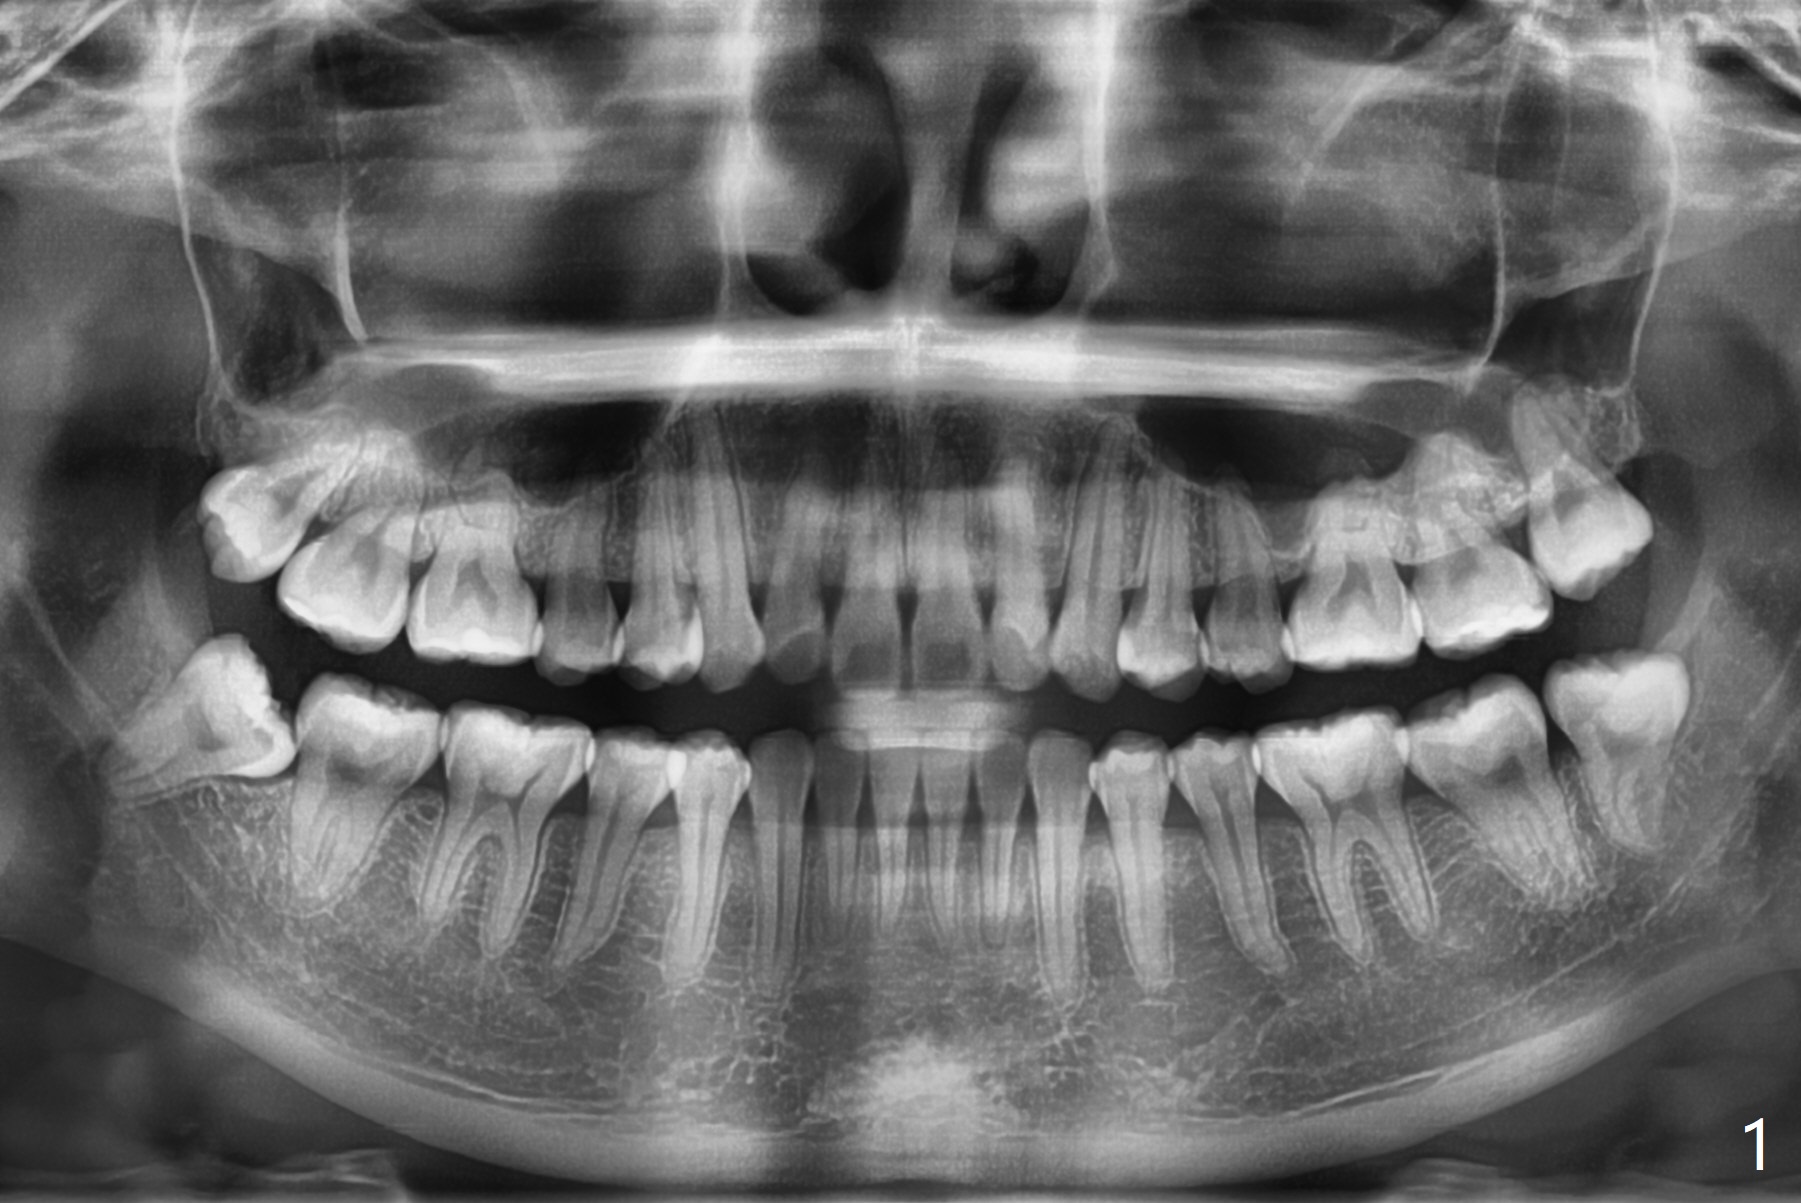

22岁女要求拔除4个智齿,右下接近下齿槽神经,必要时拍摄局部CT,如果牙根跨越神经,劈根取出,新拍摄全景片显示根尖与神经关系不是那么密切。牙槽窝底部放置底部沾有PRF液体的(结果没有这样做,因为抽血很少)Osteogen plug(一种胶原骨塞,结果放胶原塞1/2),牙槽窝近中,第二磨牙远中放置粘性骨粉,牙槽窝上部放置PRF膜(结果放胶原塞另外1/2,抽血困难),PGA缝线。左下牙槽窝放置沾有PRF液体(结果没有这样做,因为抽血很少)的胶原塞(第二磨牙远中没有缺损),覆盖PRF膜(很小一块,以及一半胶原塞),缝合。